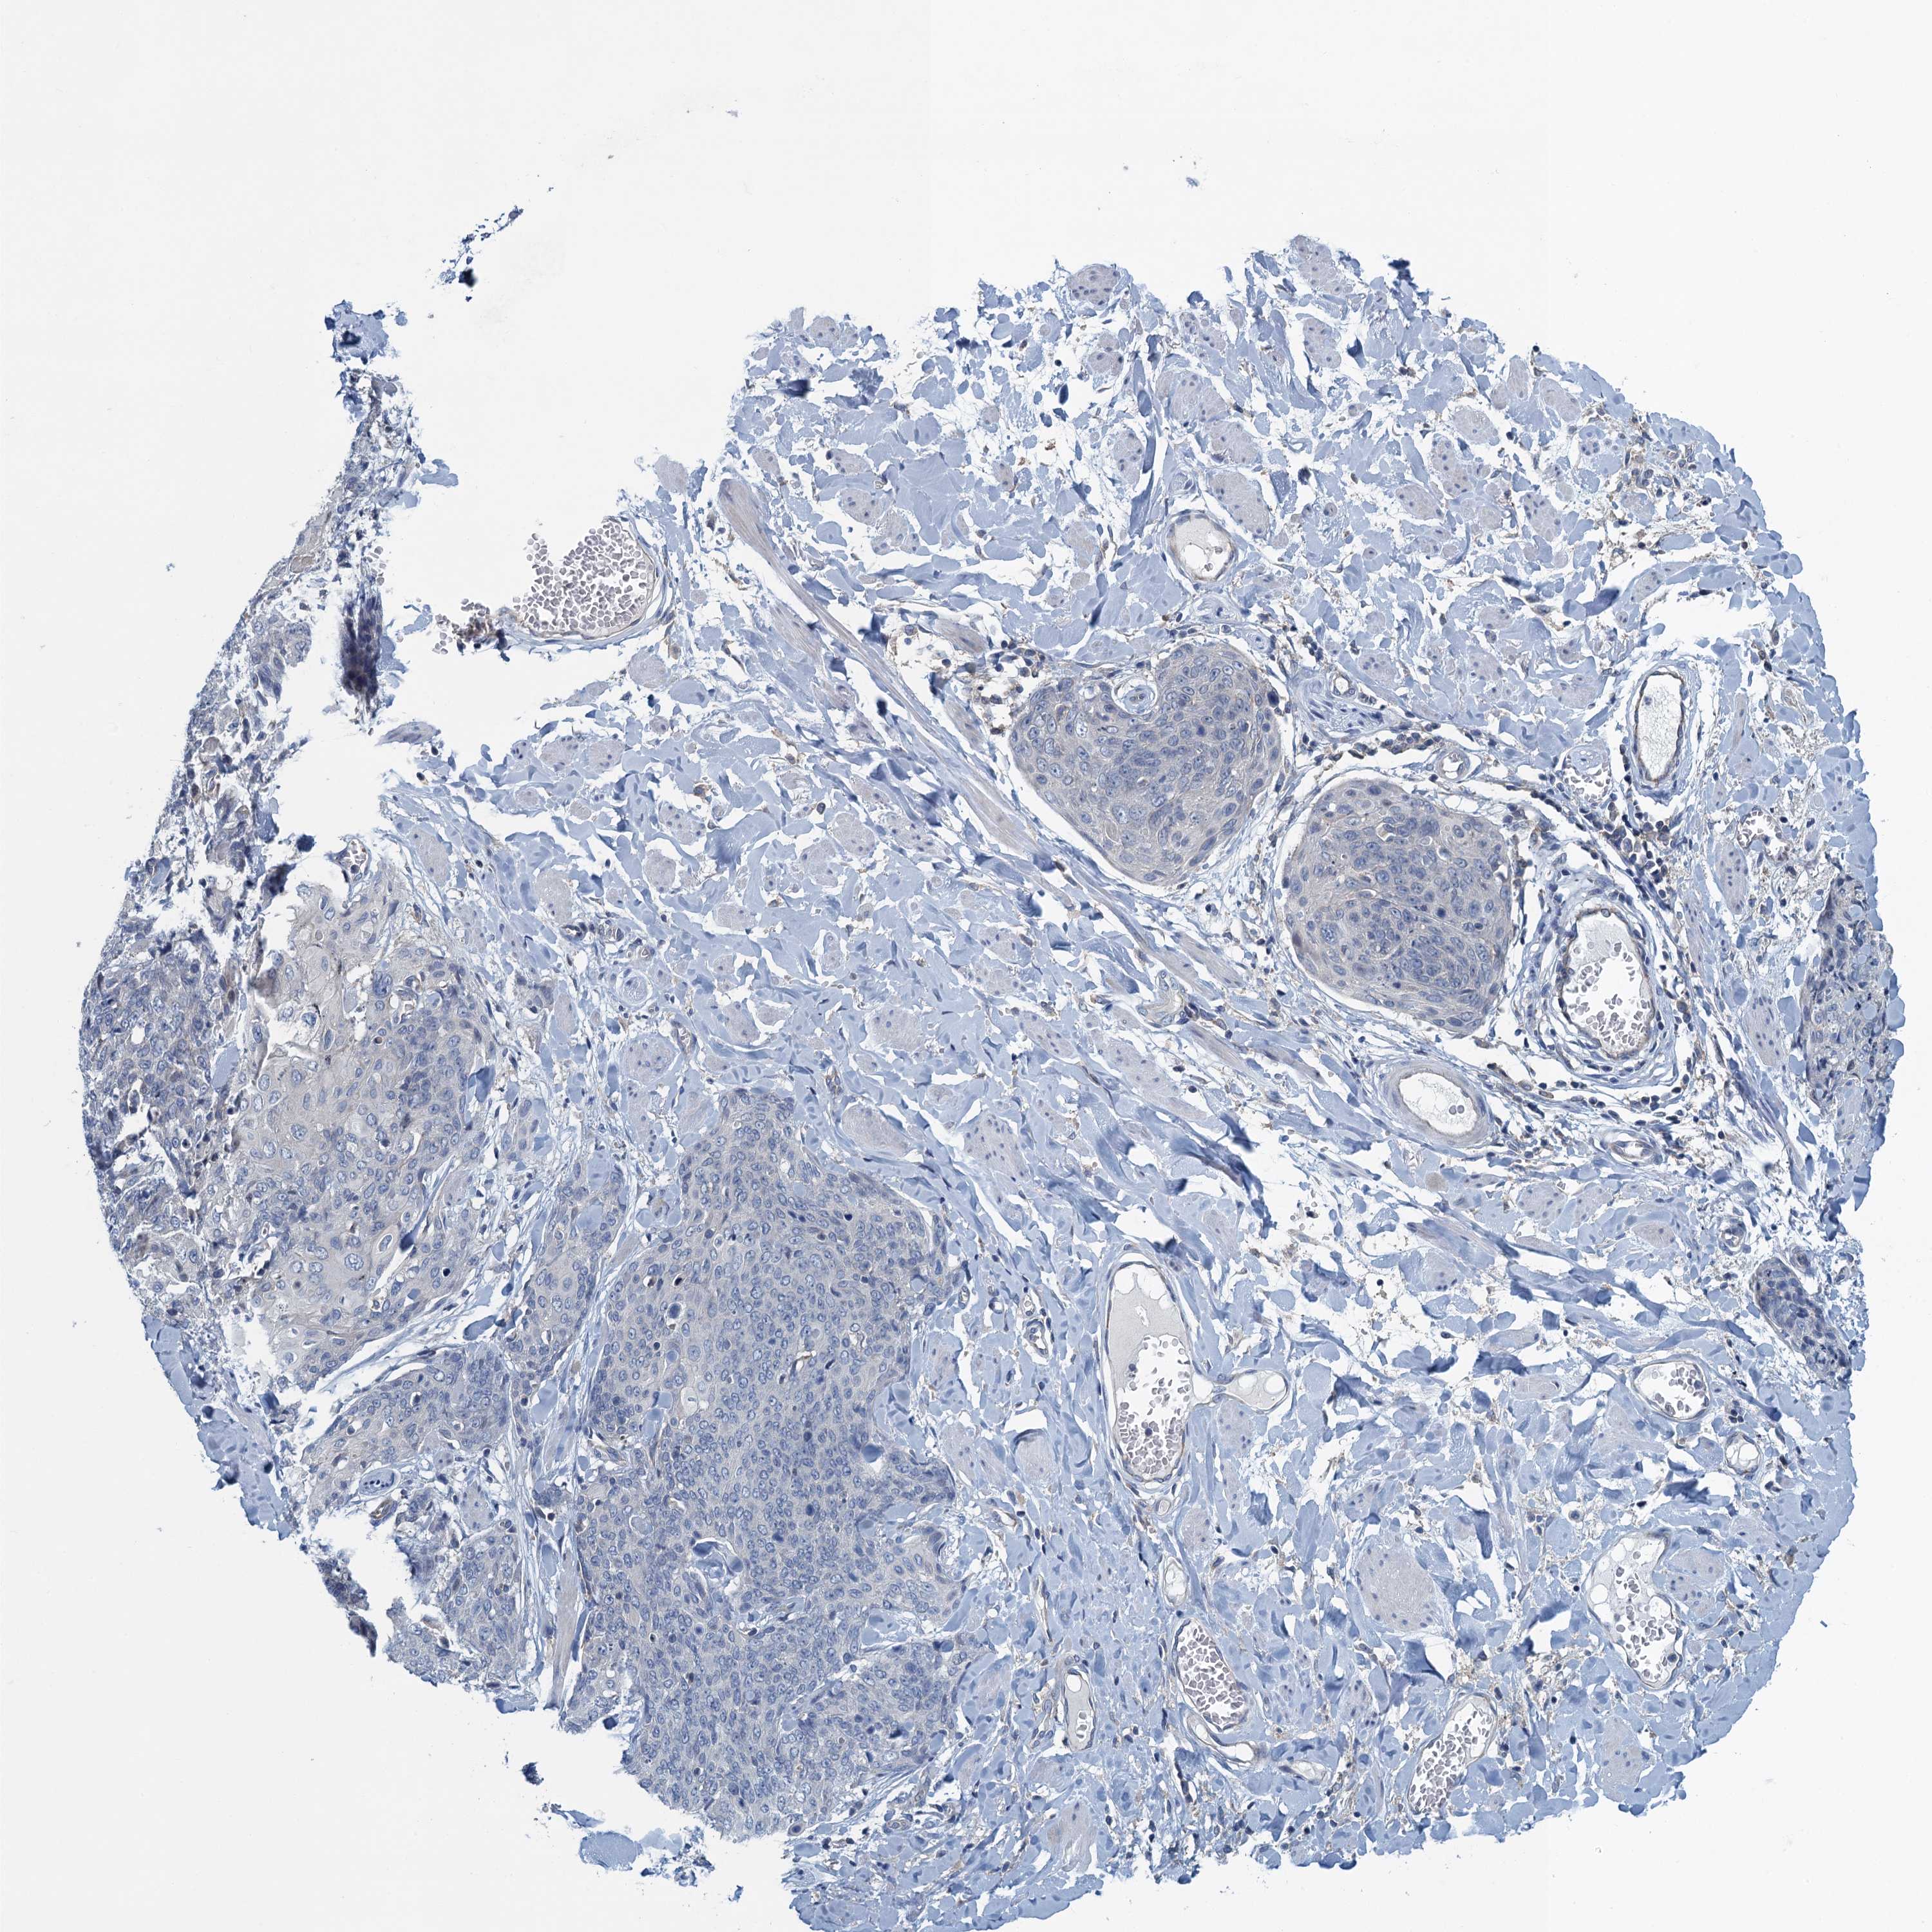

Basal cell and squamous cell cancer

SKIN CANCER - Protein expressioni

A mouse-over function shows sample information and annotation data. Click on an image to view it in a full screen mode. Samples can be filtered based on level of antibody staining by selecting one or several of the following categories: high, medium, low and not detected. The assay and annotation is described here.

Each image is clickable and will lead to virtual microscopy that enables deeper exploration of all samples and also displays staining intensity scores, fraction scores and subcellular localization as well as patient and tissue information for each sample.

Antibody HPA040772

Squamous cell carcinoma, NOS